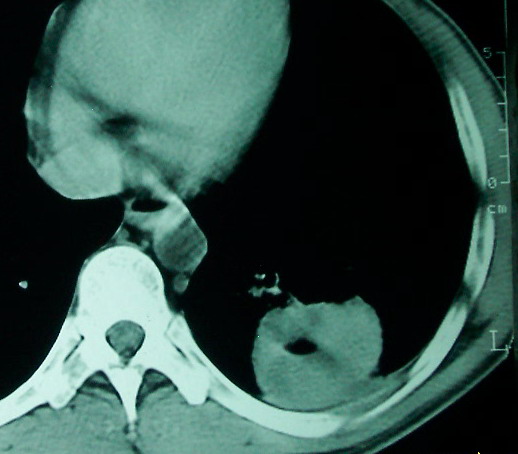

m      37y      发热   咳脓痰月余      ct肺脓肿但住院抗炎治疗后双肺内结节不知该如何解释

治疗后见左肺下野病灶较前缩小但双肺内结节影似无变化请较各位老师该如何下结论    治疗前wbc14.5 治疗后wbc 11.0

1、左下肺鳞癌伴两肺及纵隔淋巴结转移;

2、两上肺支扩伴慢性炎症。

左下肺病灶除了明显的厚壁空洞 气液平外,明显见壁结节,另两肺多发小结节,综合考虑:左下肺周围性肺癌伴肺内转移.

如果你仔细的同层面对比,你会发现所有的病灶均有比较明显的吸收、缩小。病变的形态,特别是脓肿的形态、壁的厚薄、内壁均有很大的变化,均在往好的方面发展。与临床症状、血像均符合,治疗效果比较显著,就是肺脓肿并双肺的化脓性炎症灶。